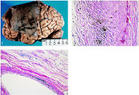

酪氨酸代謝中缺乏尿黑酸氧化酶引起的代謝遺傳病。這種病人尿中含有尿黑酸,在鹼性條件下暴露於氧氣氧化並聚合為類似於黑色素的物質,從而使尿成黑色。尿黑酸尿症是...

【診斷】尿黑酸 homogentisic acid 即2,5-二羥苯乙酸。尿黑酸尿症在患者的尿中大量存在。這種尿盛放在空氣中可變成黑色,這是由於尿黑酸自然氧化產...

病因 症狀體徵 檢查化驗 鑑別診斷 併發症尿黑酸尿與褐黃病(alkaptonuria et ochronosis)屬於常染色體隱性遺傳病。尿黑酸長期聚積在體內各器官中,可引起褐黃病。黑尿、皮膚棕...